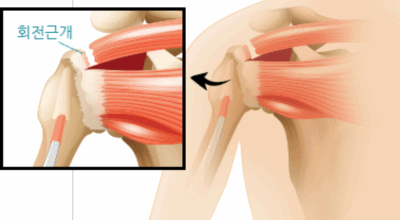

회전근개파열이란?

회전근개 증후군은 회전근개에 변형과 파열이 생긴 질환을 말해요. 회전근개란 어깨와 팔을 연결하는 4개의 근육(극상근, 극하근, 소원근, 겹갑하근) 및 힘줄로 이루어져 있는 것으로 보입니다. 어깨 근육통을 막연히 오십견으로 알고 방치하다가 치료 시기가 늦어지는 경우가 있답니다. 적절한 시기에 병원에 가는 것이 필요해요.